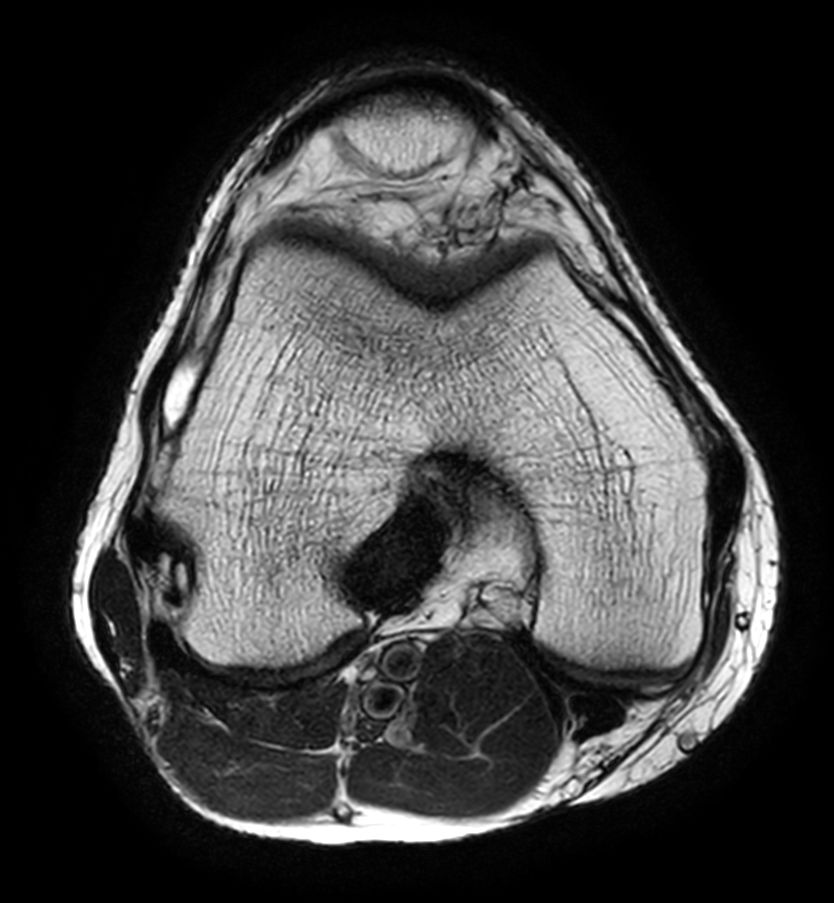

Axial T2w TSE